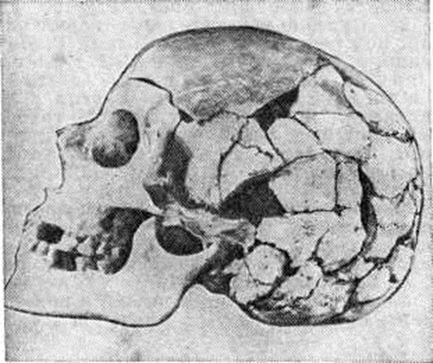

Наличие зон роста и ядер окостенения у детей приводит к определённым трудностям рентгенологическое диагностики Переломы Это прежде всего относится к локтевому суставу, в котором суставные концы костей состоят в значительной мере из хрящевой ткани и на рентгенограммах не видны, а наличие большого количества ядер окостенения и зон роста нередко является причиной грубых диагностических ошибок. Ядра окостенения и зоны роста принимаются за Переломы, и наоборот — смещённый в полость локтевого сустава медиальный надмыщелок расценивается как ядро окостенения и своевременно не извлекается из полости локтевого сустава. У детей, особенно у новорожденных, при сращении Переломы наблюдается образование обширной мозоли, при рентгенографии нередко принимаемой за саркому. Рентгенологические распознавание эпифизеолиза возможно лишь с возраста, когда появляются ядра окостенения, и в том случае, если Переломы сопровождается смещением. При эпифизеолизе линия Переломы часто проходит на границе зоны предварительного обызвествления эпифизарного хряща и костной части метафиза так, что при этом отламывается клиновидный кусочек кости от метафиза. В чистом виде эпифизеолиз наблюдается обычно в области шейки бедренной кости и часто осложняется асептическим некрозом её головки.